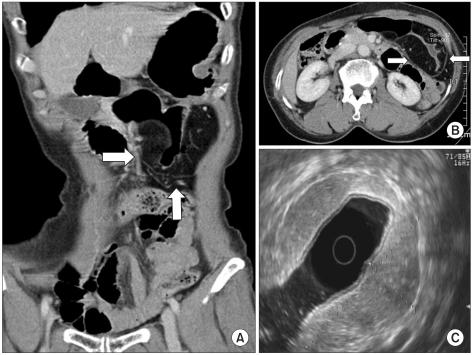

Gastric lipomatosis is an extremely rare condition. We present a case of a 69-year-old woman admitted with epigastric soreness. Computerized tomography (CT) revealed extrinsically compressing, fat-containing mass lesions on the entire gastric wall of the antrum and body except for the lesser curvature. A subtotal gastrectomy was performed. Pathology findings confirmed a gastric lipomatosis with multiple gastric ulcerations and extensive disruptions of the muscular layers. This case and reports of other gastric lipomatosis cases indicate that CT should be used to characterize large submucosal masses because CT can show the specific nature and extent of the disease. We believe that surgical treatment is the most appropriate treatment for symptomatic gastric lipomatosis that shows extensive gastric involvement, or when there are multiple gastric lipomas.